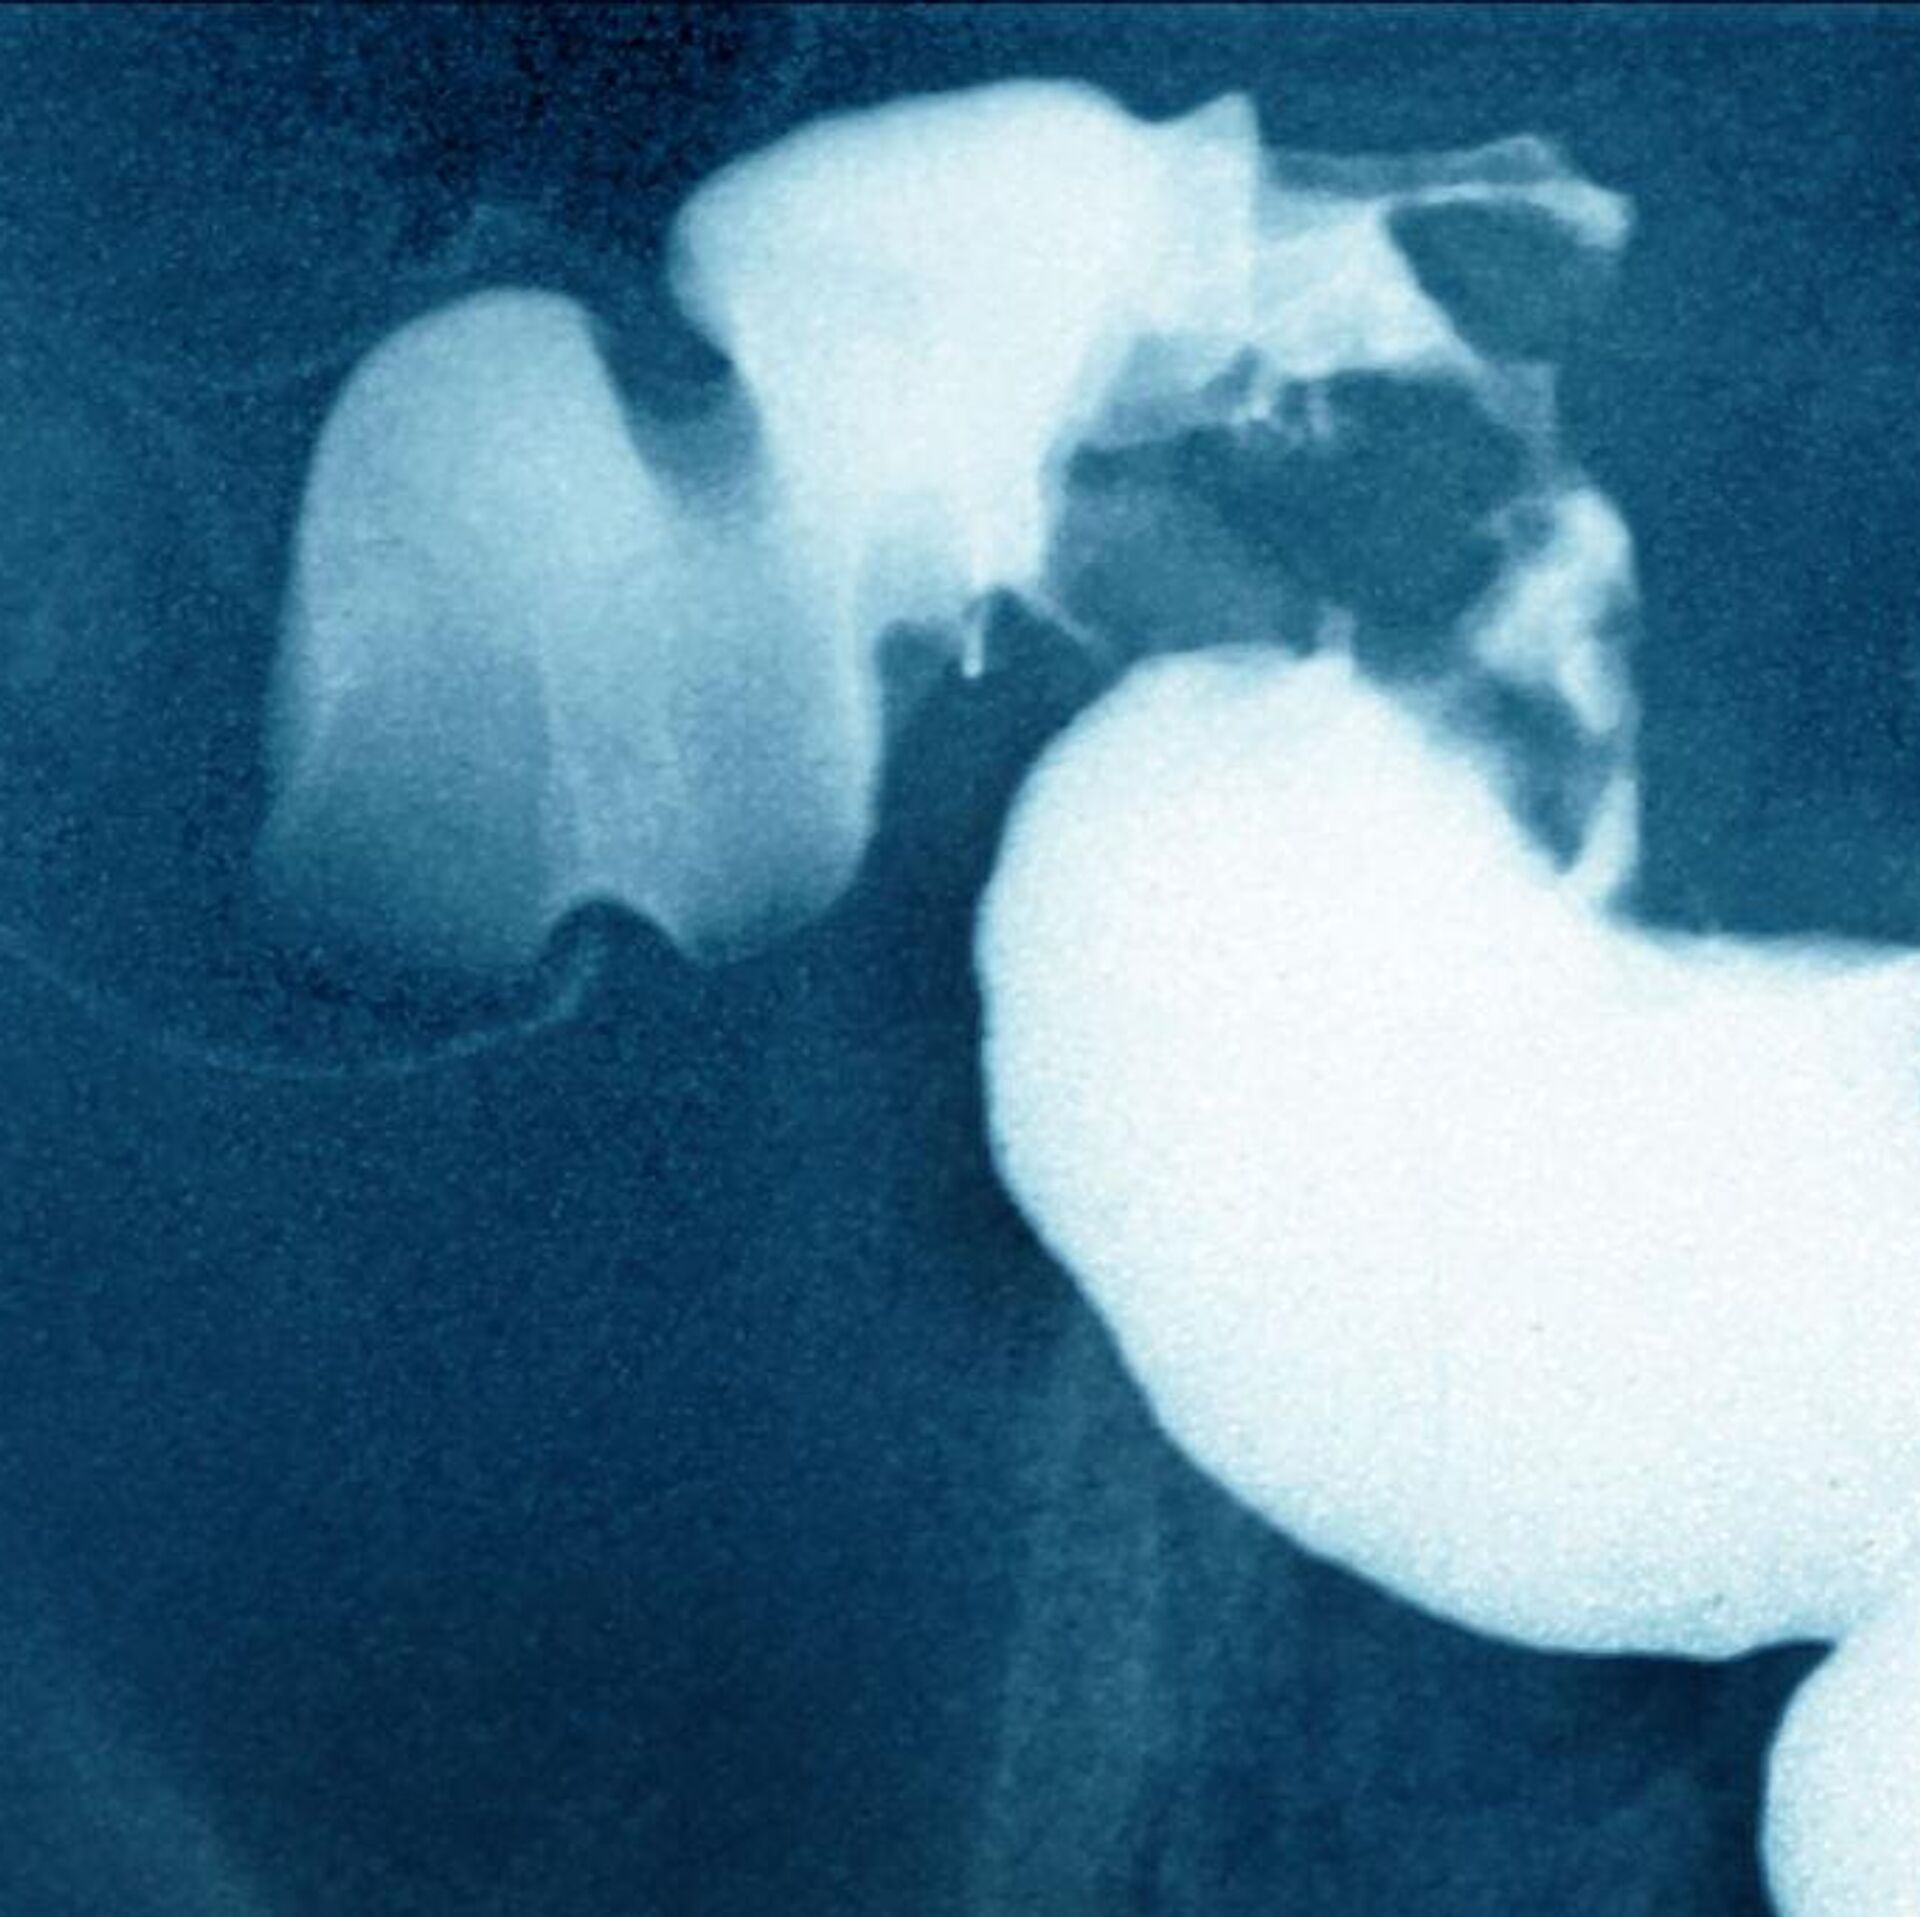

دراسة جديدة تكشف علاقة الزبادي بسرطان القولون

© Getty Images / BSIP / Contributorسرطان القولون

سرطان القولون - سبوتنيك عربي, 1920, 22.02.2025

توصلت دراسة حديثة إلى أن تناول علبتين من الزبادي أسبوعيًا قد يحمي الأمعاء من بعض أنواع السرطان وخاصة سرطان القولون.

ذكر ذلك موقع "ساينس أليرت"، اليوم السبت، مشيرا إلى أن الدراسة تم إجراؤها على فترة طويلة، مشيرة إلى أنها أوضحت أمورا كانت محل شكوك بالنسبة لعلاقة الزبادي بتقليل فرص الإصابة بهذا المرض.

فبينما كانت الدراسة التي يتم إجراؤها بصورة عامة لا تظهر علاقة بين استهلاك الزبادي وسرطان القولون والمستقيم عمومًا، فإن إجراء الأبحاث بصورة أكثر تفصيلا سمح بالتوصل لنتائج جديدة.

وتقول الدراسة إن الأشخاص الذين تناولوا علبتين أو أكثر من الزبادي أسبوعيا، كانوا أقل عرضة للإصابة بأورام إيجابية بنسبة 20 في المئة، مقارنة بمن يستهلكون أقل من علبة واحدة شهريًا.

وكانت هذه العلاقة أقوى بالنسبة للأورام في الجزء العلوي من الأمعاء، مما يشير إلى دور محتمل للبكتيريا في الحد من تطور هذه الأورام.

ويرى الباحثون أن هذه البكتيريا قد تمتلك خصائص مضادة للأكسدة والالتهابات وتعزز المناعة، مما قد يساعد في زيادة قدرة الجسم على مقاومة المرض.

وتعزز هذه الدراسة فرضية أن استهلاك الزبادي قد يكون عاملًا وقائيًا ضد سرطان القولون المرتبط بضعف الحاجز المعوي، لكنها تستدعي المزيد من الأبحاث لفهم الآليات الخاصة بهذا الأمر.